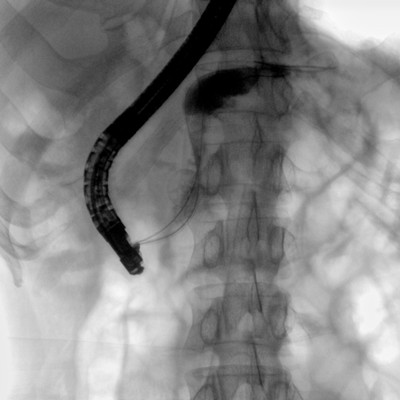

消化內科: ERCP、PTCD、肝臟介入(TACE、灌注)、食管支架等。

優質平板探測器、可靈活升降調節SID、獨特圖像處理系統、高品質濾線柵,大視野成像清晰不失真。